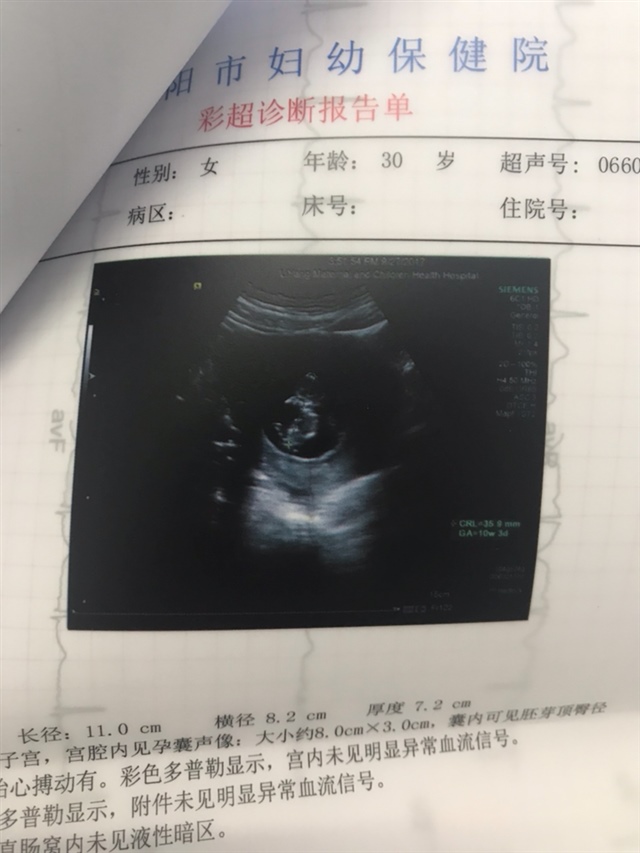

宝宝2个月9天

孕9周+4天